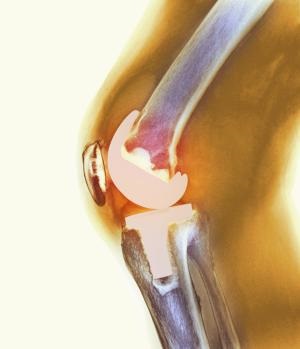

imagine cu raze X a articulației genunchiului infectat, încercați să-și imagineze că, în această imagine prea mult?

luxatii recurente sau fracturi

Datorita echipamentului modern al implantului este pus în locul îmbinării deteriorate cu o precizie milimetrică, cu ajutorul imaginilor pe computer se efectuează verificarea cinematicii în poziția îndoită / neîndoită. 1-1,2% din finisaje repetate luxație sau fractură a implantului. În cazuri rare, problema este cauzată de instalarea incorectă sau proteză de slabă calitate, 98% dintre pacienți crea propriile lor probleme, ignorând recomandările de reabilitare.

Deci, ce se întâmplă atunci când un prejudiciu primit, omul a căzut exemplul. Au nevoie de o intervenție chirurgicală de revizuire.